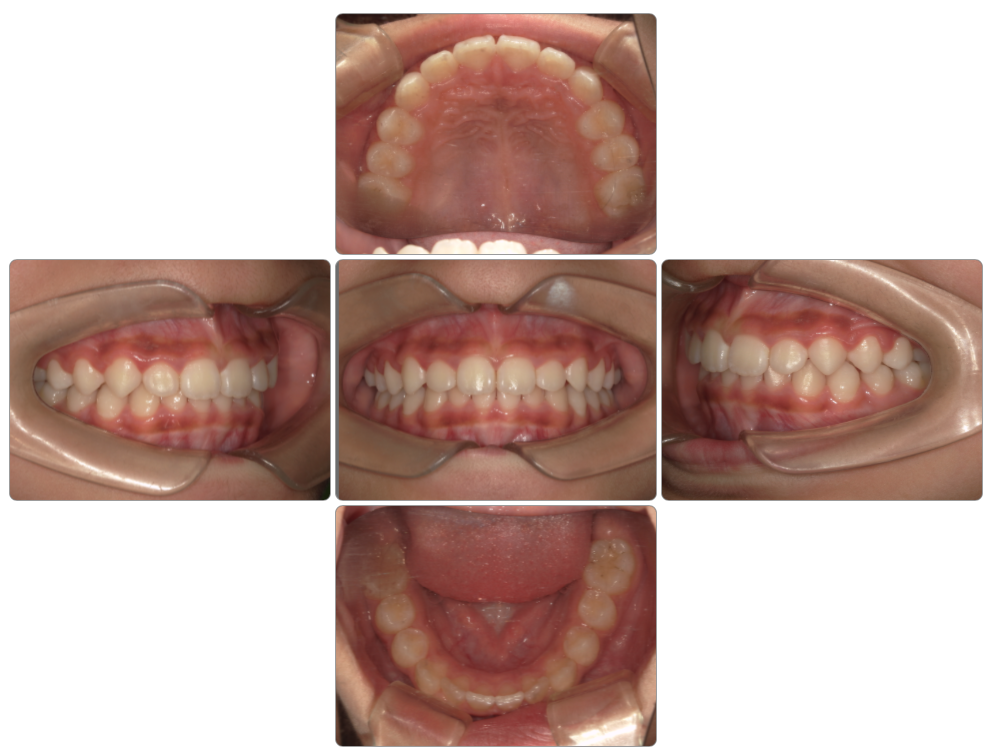

Before

after

| 初診時 | 11歳6ヵ月 |

| 治療期間 | 2年半 |

| 費用 | ¥1,100,000 |

| 使用装置 | マイオブレイス・インビザライン |

| リスクと副作用 | |

| 原因と考察 | MRCとインビザラインの併用症例です。MRCにおいて顎の成長を促し抜歯を回避しながらインビザラインで歯並びを整えました。このように歯列に対してアプローチした矯正では後戻りリスクが高いので保定装置は欠かせません。 |